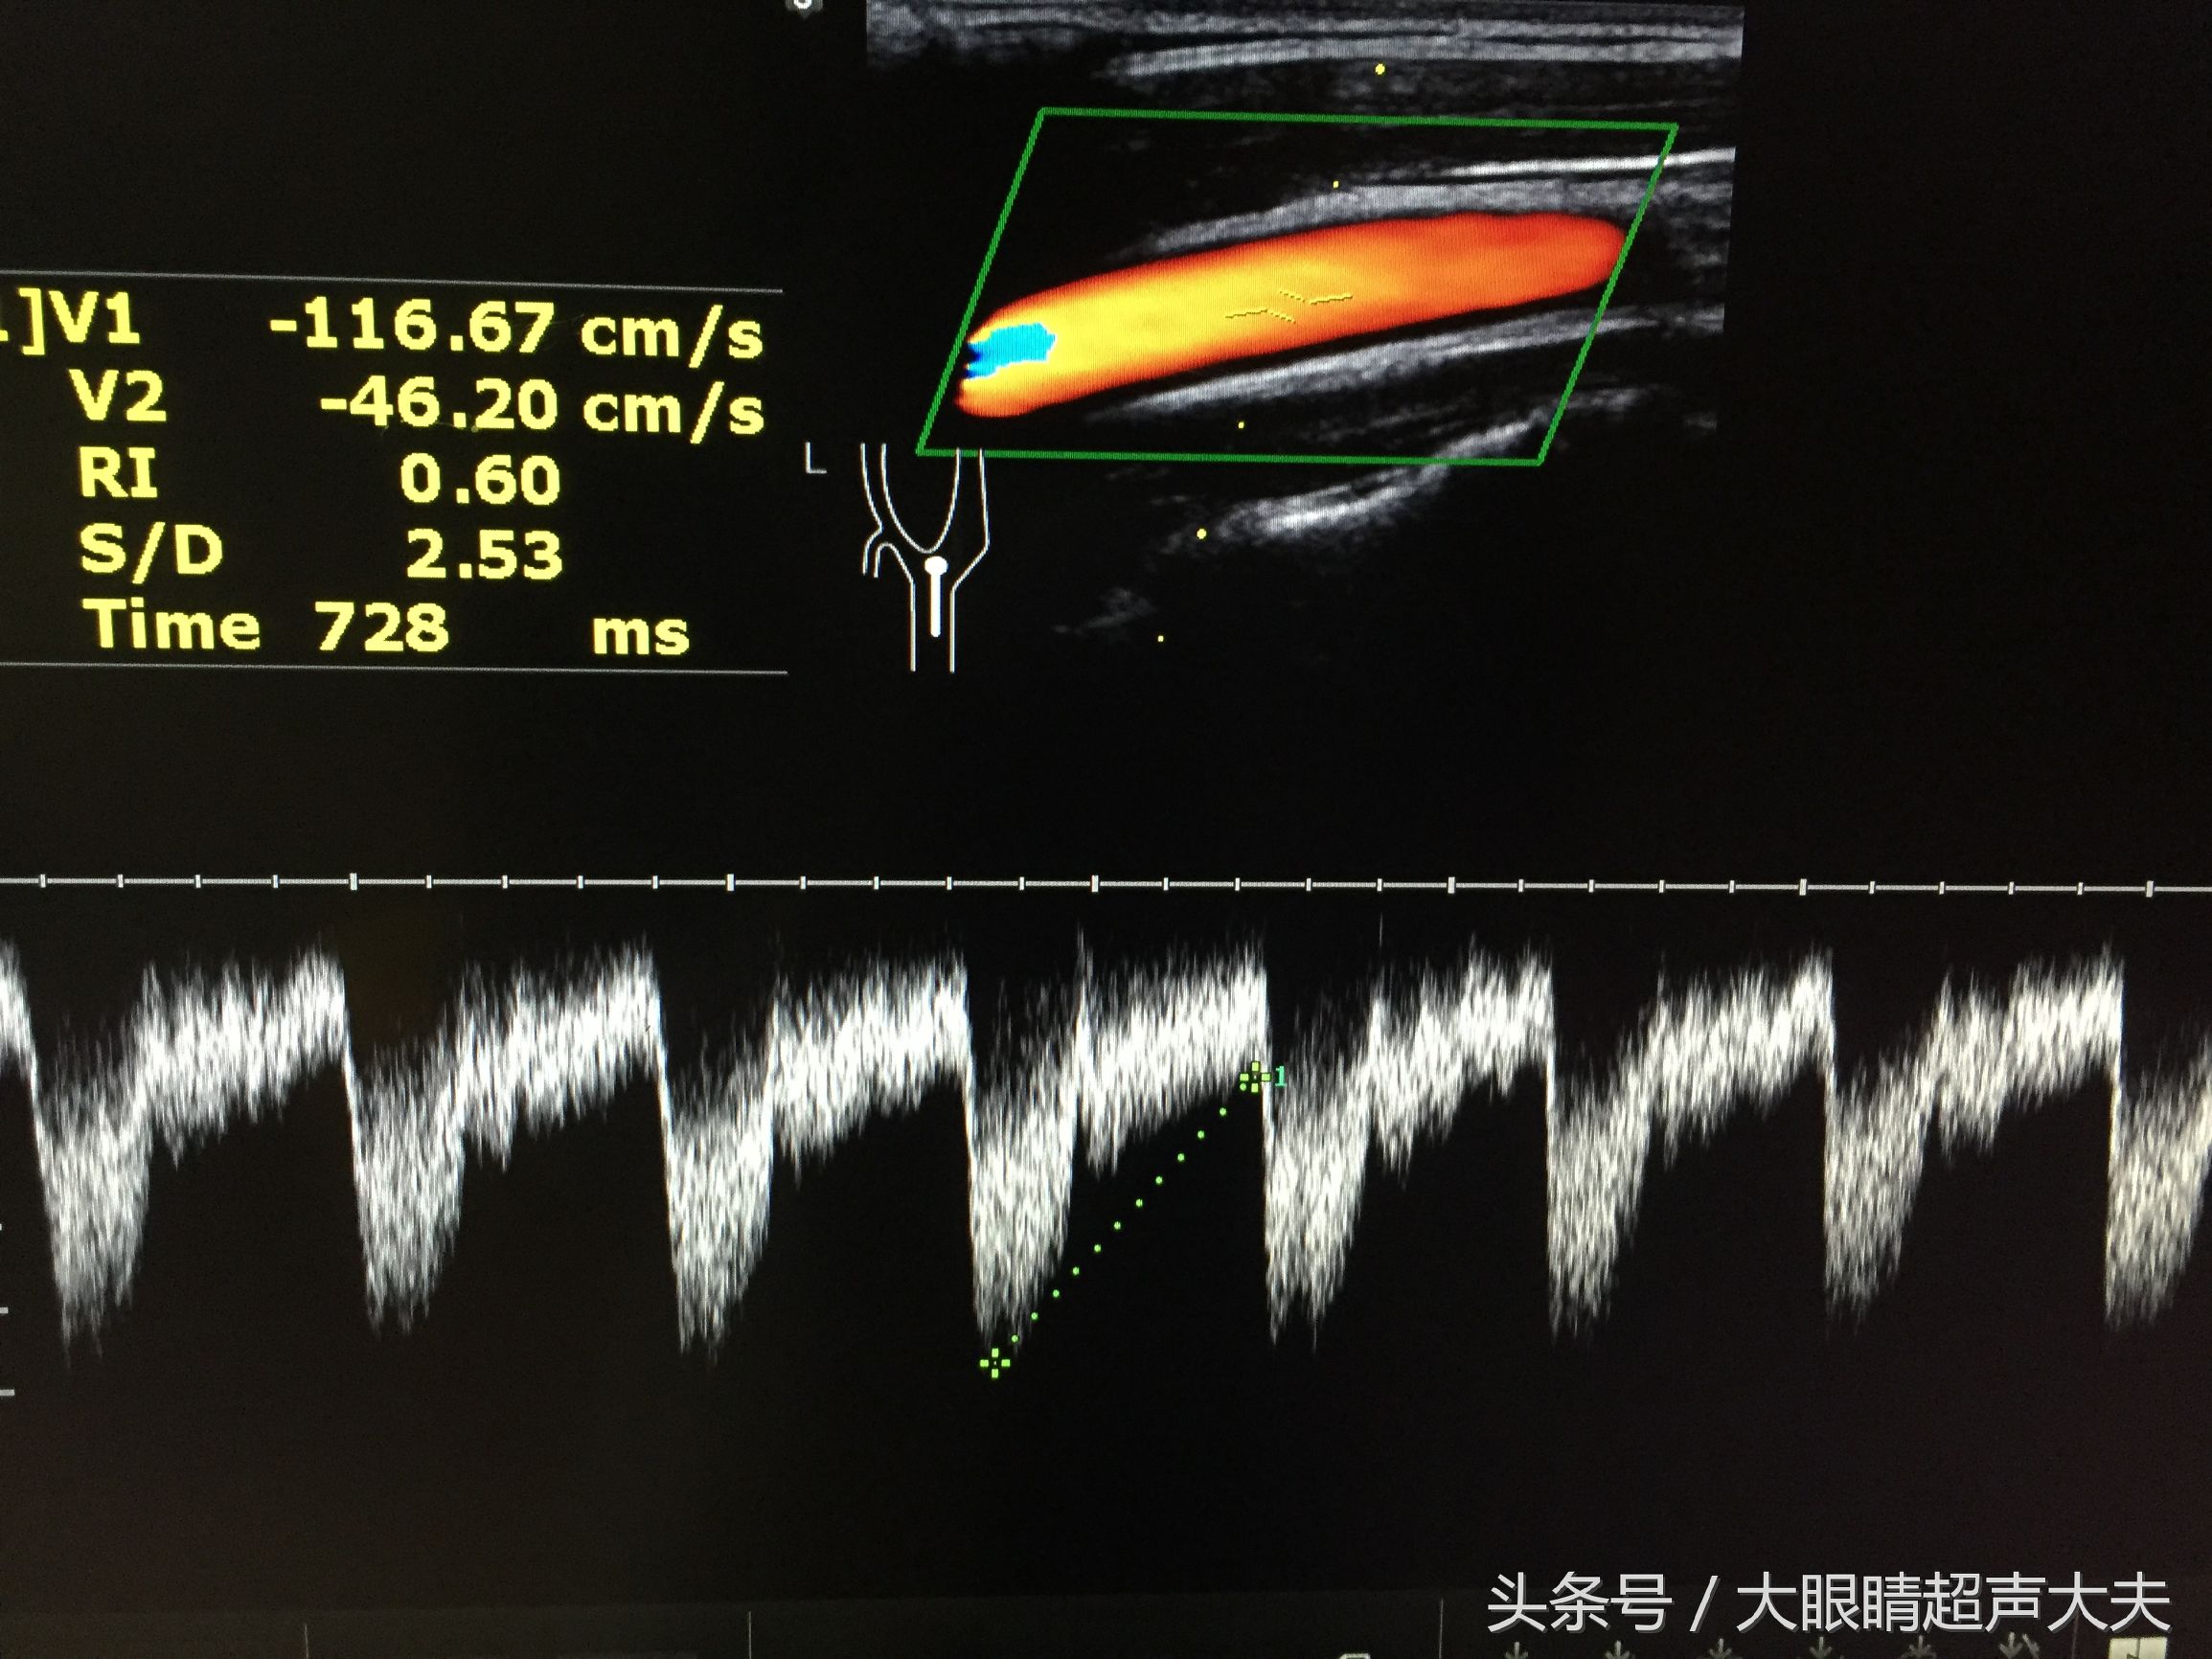

。颜色的亮度代表着血流速度。医生再通过机器打出频谱,经过测量,可以得到某血管的血流速度,血流阻力,压差……等等各种指标。所以,彩超可以在黑白B超的基础上,又给医生提供了更多的信息,这样更加有利于疾病的诊断。

下图是血管超声: